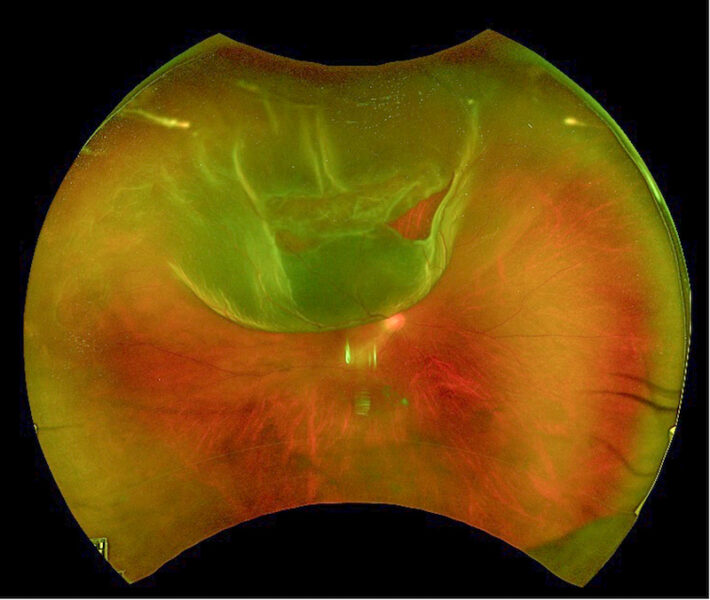

To examine the retina, the ophthalmologist needs to dilate the pupil. They then use a device called a binocular indirect ophthalmoscope to examine the retina in detail. If a retinal detachment is present, they will see the affected area floating away from the inner wall of the eye. They can assess the extent of the detachment and document the location of any retinal tears.

This image above depicts a retinal detachment in the right eye. We can see a retinal tear at the one o’clock position. The retinal detachment extends from the 10 to about two o’clock positions. This patient would have a sudden onset of eye floaters and about half the vision blocked by a shadow.